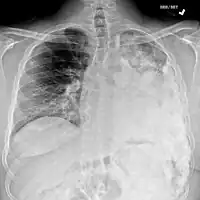

Osteosarcoma of the distal femur

Metastatic osteosarcoma to the left chest

Most times, the early signs of osteosarcoma are caught on X-rays taken during routine dental check-ups. Osteosarcoma frequently develops in the mandible (lower jaw); accordingly, dentists are trained to look for signs that may suggest osteosarcoma. Even though radiographic findings for this cancer vary greatly, one usually sees a symmetrical widening of the periodontal ligament space. If the dentist has reason to suspects osteosarcoma or another underlying disorder, he or she would refer the person to an Oral & Maxillofacial surgeon for biopsy. A biopsy of suspected osteosarcoma outside of the facial region should be performed by a qualified orthopedic oncologist. The American Cancer Society states: "Probably in no other cancer is it as important to perform this procedure properly. An improperly performed biopsy may make it difficult to save the affected limb from amputation." It may also metastasise to the lungs, mainly appearing on the chest X-ray as solitary or multiple round nodules most common at the lower regions.